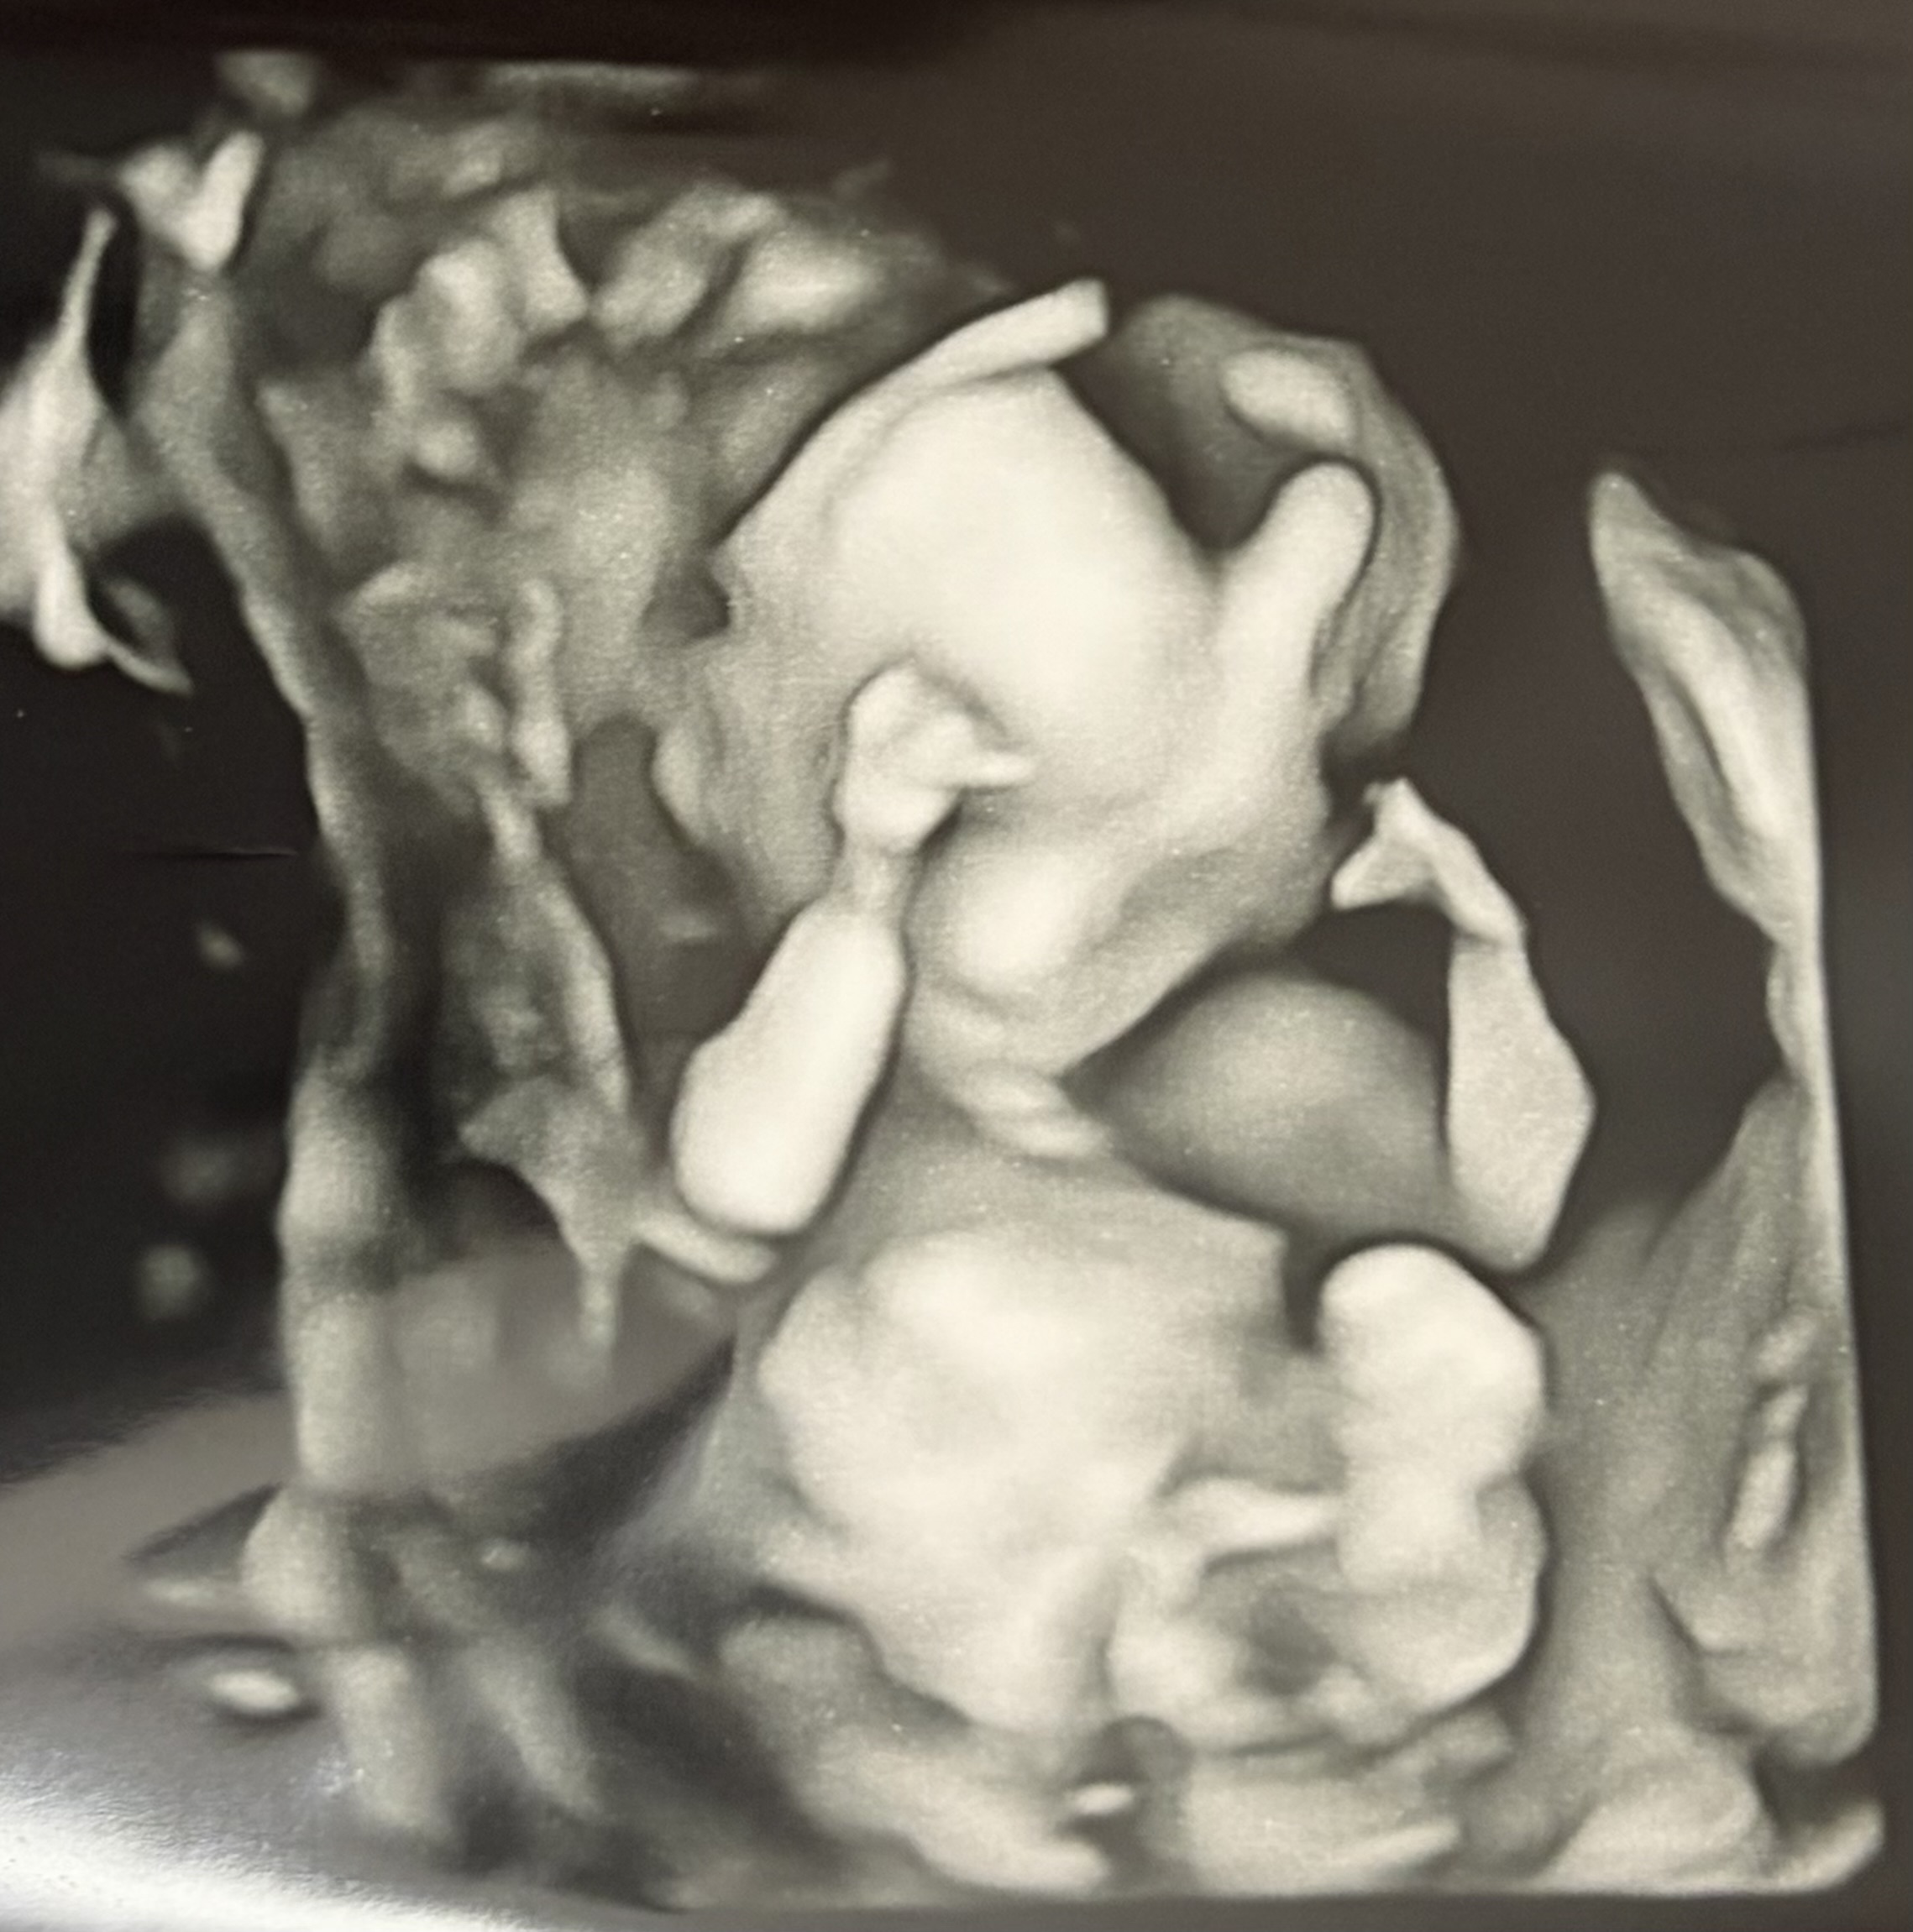

赤ちゃんの心臓エコーについて

大腿骨が短かったこともあり、

心臓のエコーを約1時間かけて丁寧に診てもらいました。

- 大きな異常は見当たらない

- ただ、心臓の周りの血管が通常とは少し違う場所にある

- それが病気なのか、個性なのかは判断できない

赤ちゃんがもう少し大きくなったら、

再度、8週間後に検査をする予定です。